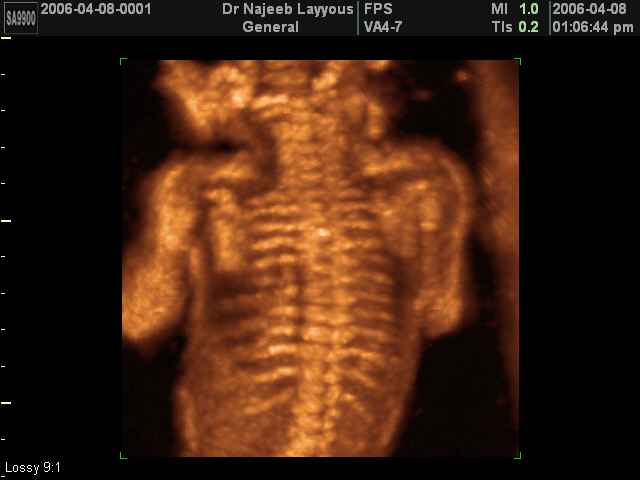

- 3D Photos échographie du squelette du fœtus

3D Photos échographie du squelette du fœtus | Dr N Layyous